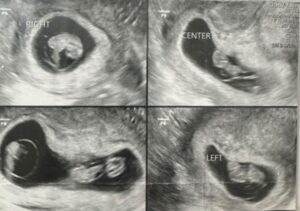

エコー写真①(@mitsugoma0123さんより提供)

2回目の健診で三つ子だと分かったママさん。ママさん自身が双子のため、双子を授かれたらいいなと思っていたところ、まさかの三つ子で驚いたといいます。